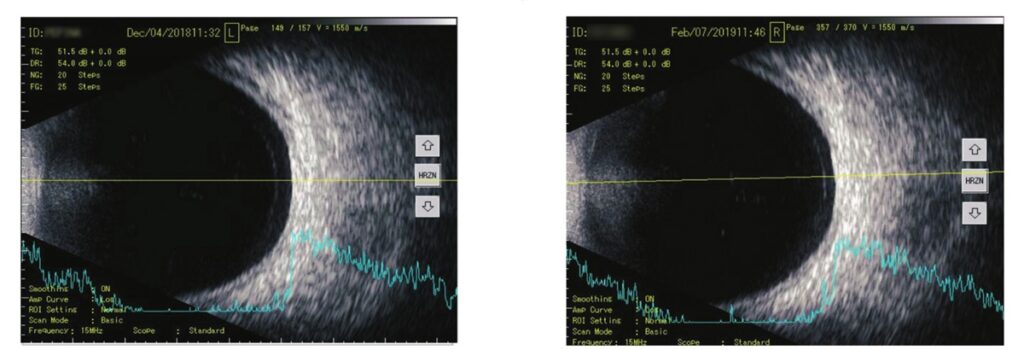

De klinische studie werd uitgevoerd bij 32 patiënten van 37 tot 57 jaar, bij wie door middel van oogechografie glasvochttroebelingen waren vastgesteld. De patiënten werden in twee groepen verdeeld: 16 patiënten met symptomatische mouches volantes kregen gedurende drie maanden VitroCap®, de andere 16 (zonder visuele klachten door hun floaters) werden niet behandeld.

Resultaten: In het onderzoek werden significante verbeteringen aangetoond in zowel subjectieve visuele klachten (vragenlijst) als objectieve parameters (oogechografie) na de behandeling met VitroCap®.

De observaties bevestigden dat het gebruik van VitroCap® het visuele comfort verbetert en in de meeste gevallen de subjectieve klachten van patiënten over mouches volantes vermindert. Bovendien was er een zichtbare trend naar een afname van de glasvochttroebelingen en een verbetering van hun kwalitatieve eigenschappen.

Studieopzet: In dit klinisch onderzoek werden 62 patiënten van 40 tot 64 jaar geïncludeerd om de werkzaamheid van VitroCap® bij de behandeling van glasvochtdegeneratie te beoordelen. De aanwezigheid van glasvochttroebelingen werd bevestigd met behulp van oogechografie.

De veranderingen die bij het spleetlamponderzoek en de B-mode-glasvochtechografie werden waargenomen, waren in beide groepen vergelijkbaar. Daarnaast werden geen significante veranderingen in de visuele functie vastgesteld.